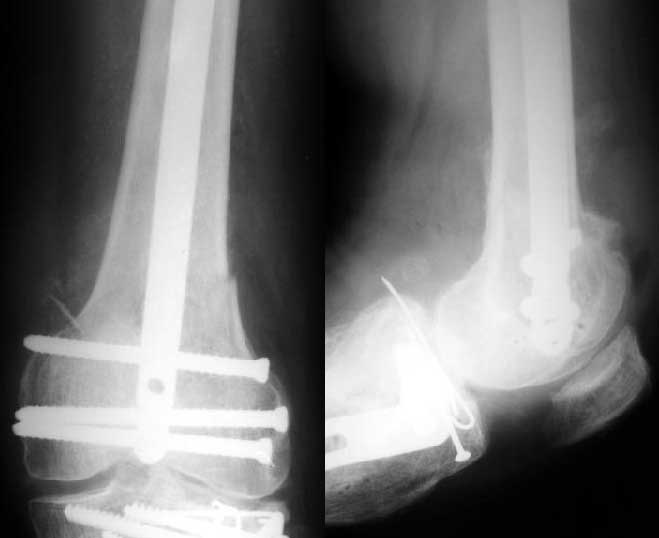

Sorry but I've just prepared postop images - attached. A solid 13 mm nail was used. A few degrees of recurvation appears to be which i missed on image intensifier. I'm still uncertain about

advantages/disadvantages of ante/retrograde nailing for such fractures.

The antegrade nail in the case shown is probably into the knee joint slightly.

TAC> The antegrade nail in the case shown is probably into the knee joint slightly.

Not in this case. Though i have a couple of similar cases with 3-4 mm prominince of the nail - looks asymptomatic or covered by pre-existing problems.